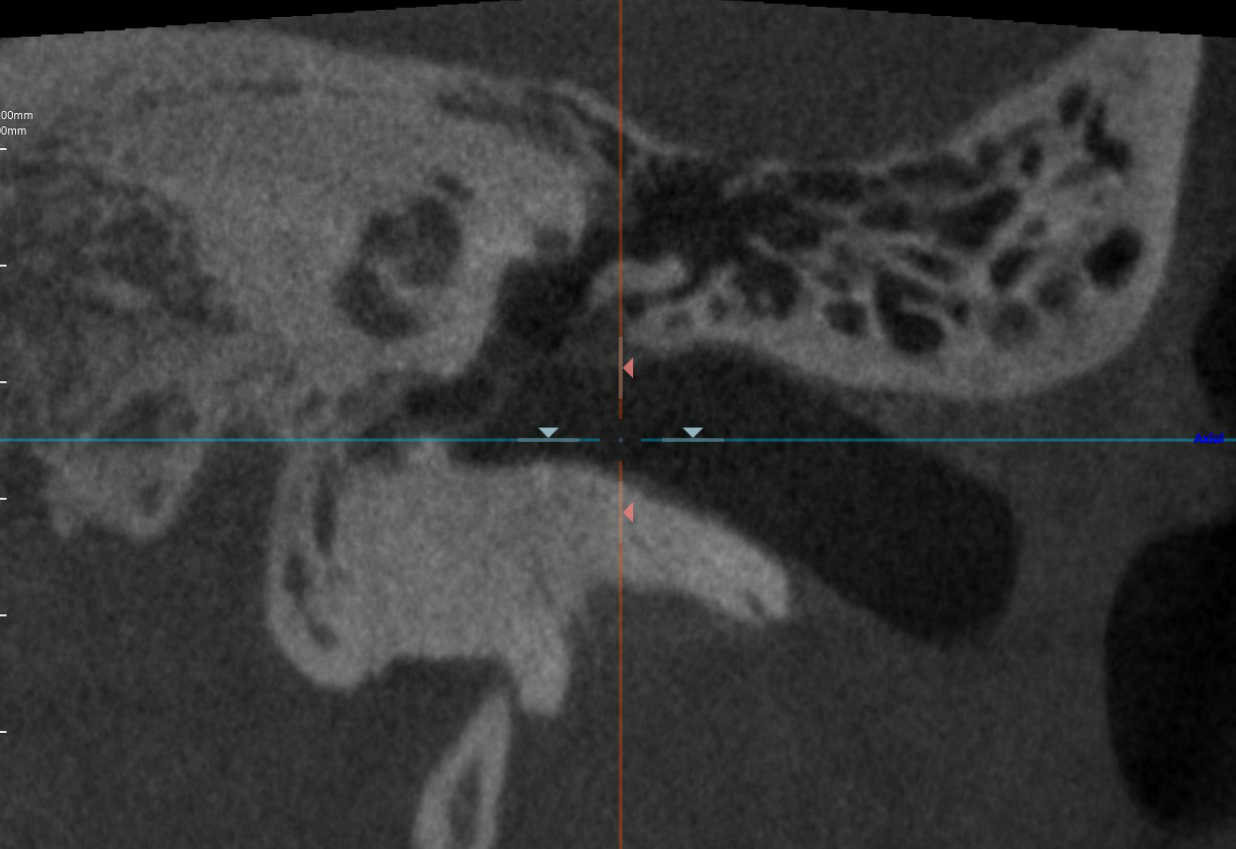

中耳CT

中耳/内耳CT

- 真珠腫性中耳炎を疑う場合

- 中耳や内耳の奇形を疑う場合

- 進行性の難聴がある場合

- 原因不明の伝音難聴 など